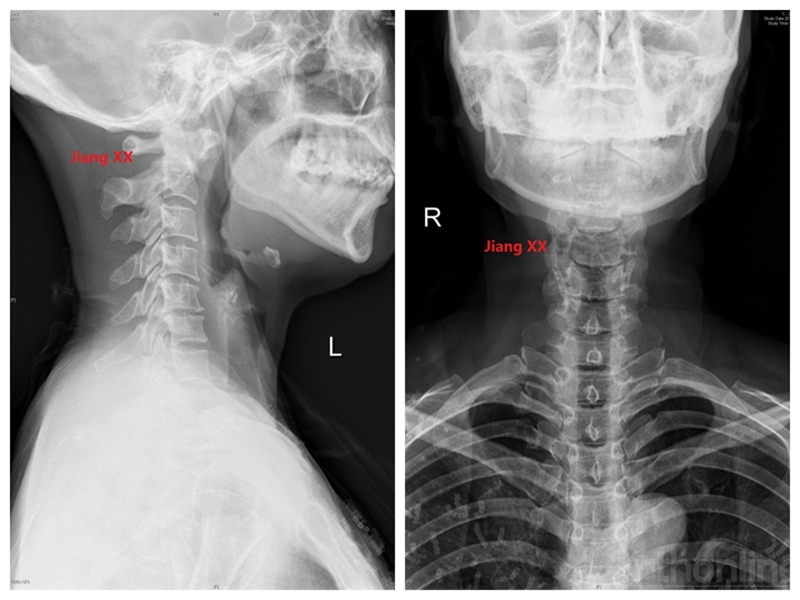

病例二:患者女性,58岁,主因“颈部疼痛伴转头受限半年”入院,诊断为寰枢椎半脱位。

术前X线

术后X线